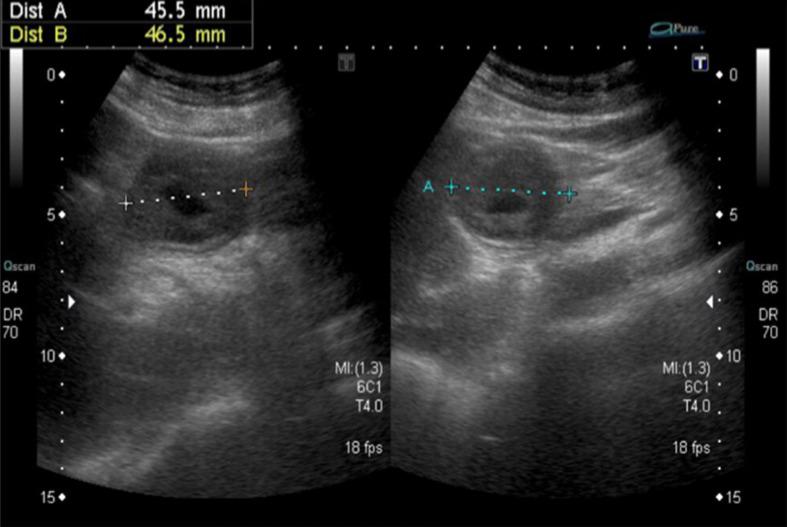

An 84-year-old woman presented with symptoms of postprandial fullness with nausea and occasional vomiting for a month. Initially, she visited a local clinic for help, where abdominal sonography revealed a space-occupying lesion around the liver, so she was referred to our hospital for further confirmation. Abdominal sonography was repeated, which revealed a mass with an alternating concentric echogenic lesion. Esophagogastroduodenoscopy (EGD) was performed under the initial impression of gastric cancer with central necrosis and showed a tortuous distortion of gastric folds down from the lesser curvature side to the duodenal bulb with stenosis of the gastric outlet. EGD was barely passed through to the 2nd portion of the duodenum and a friable ulcerated mass was found. Several differential diagnoses were suspected, including gastroduodenal intussusception, gastric cancer invasion to the duodenum, or pancreatic cancer with adherence to the gastric antrum and duodenum. Abdominal computed tomography for further evaluation was arranged and showed gastroduodenal intussusception with a long stalk polypoid mass 5.9 cm in the duodenal bulb. Under the impression of gastroduodenal intussusception, ESD was performed at the base of the gastroduodenal intussusception; unfortunately, a gastric perforation was found after complete resection was accomplished, so gastrorrhaphy was performed for the perforation and retrieval of the huge polypoid lesion. The gastric tumor was pathologically proved to be a GIST. After the operation, there was no digestive disturbance and the patient was discharged uneventfully on the 10th day following the operation.

一名84岁女性出现餐后饱胀、恶心及偶尔呕吐症状1个月。最初,她前往当地诊所求助,腹部超声检查发现肝脏周围有占位性病变,因此被转诊至我院进一步确诊。再次进行腹部超声检查,发现一个具有交替同心回声病变的肿块。在初步诊断为伴有中央坏死的胃癌的情况下进行了食管胃十二指肠镜检查(EGD),结果显示胃皱襞从胃小弯侧向十二指肠球部呈扭曲状向下延伸,胃出口狭窄。EGD勉强通过至十二指肠第二部,发现一个易碎的溃疡肿块。怀疑有多种鉴别诊断,包括胃十二指肠套叠、胃癌侵犯十二指肠或胰腺癌累及胃窦和十二指肠。安排了腹部计算机断层扫描进一步评估,结果显示胃十二指肠套叠,十二指肠球部有一个长蒂息肉样肿块,大小为5.9 cm。在胃十二指肠套叠的诊断下,在胃十二指肠套叠的基部进行了ESD;不幸的是,在完成完全切除后发现胃穿孔,因此对穿孔进行了胃缝合术并取出了巨大的息肉样病变。胃肿瘤经病理证实为GIST。术后无消化功能障碍,患者术后第10天顺利出院。